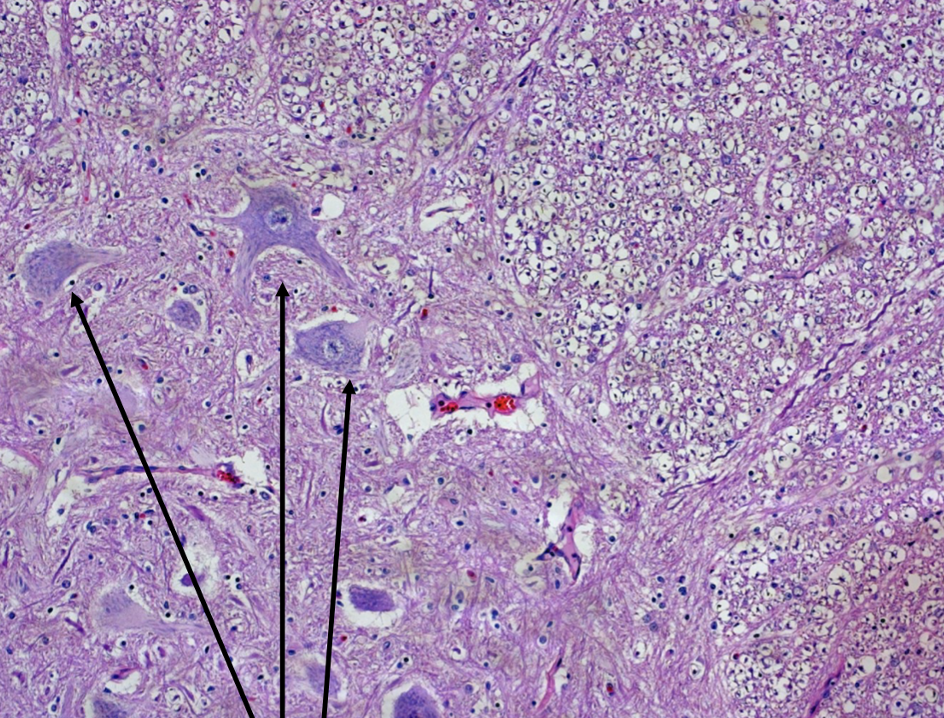

Nissl substance / nissl bodies at arrow tipis